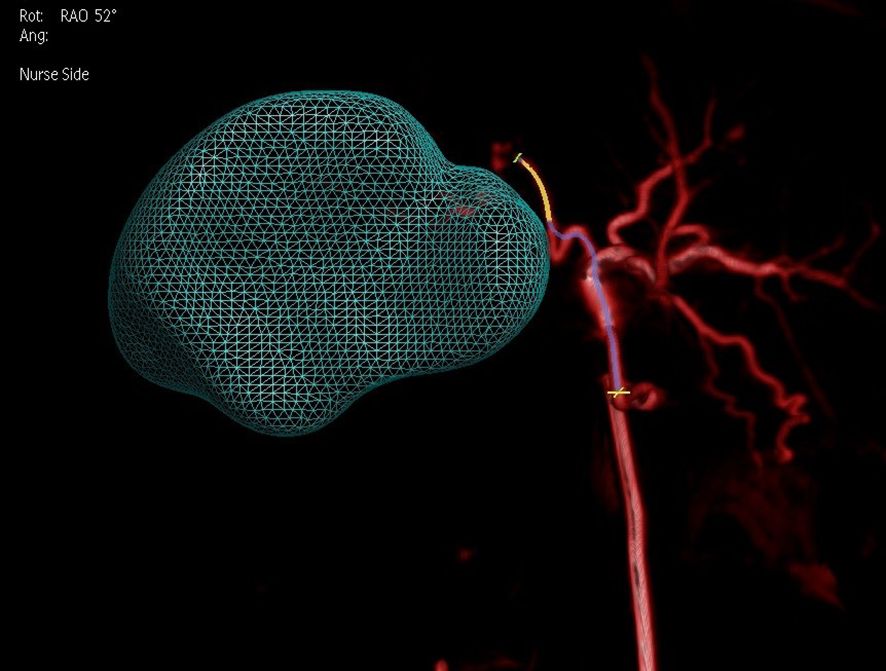

This study utilized dual CBCT technology to precisely locate tumors and their feeding vessels. Figure 6 and Figure 7 showed dual CBCT from the same cross-section obtained after super-selection, used to construct a 3D reconstruction model of the tumor and its blood supply vessels. The 3D model, viewed from a left anterior oblique position, clearly displays the spatial relationships between the tumor and its vessels. This detailed reconstruction significantly enhanced the precision and effectiveness of subsequent interventional procedures. Figure 8 illustrated the confirmation process conducted via arteriography after super-selection, verifying vascular localization and providing reliable data for subsequent operations.

Figure 7

Abstract digital art featuring a blue wireframe mesh resembling an organic shape against a black background. A winding red line loops and twists from the mesh structure, adding contrast.

Figure 7. Dual CBCT used to create a 3D reconstruction model of its blood supply vessels (viewed from a left anterior oblique position) after successful super-selection.

By adjusting the angle, better identification of tumor-feeding arteries was achieved, assisting operators in accurately locating their entry points for precise catheter insertion. The angle was set to 52° right anterior oblique in the fused model, as shown in Figure 9. Post-90Y-SIRT, nuclear medicine verification was performed, as shown in Figure 10.

Figure 9

Medical imaging illustration showing a three-dimensional, translucent mesh structure in teal overlaying an arterial network in red. The background is dark, with some annotations in white text indicating rotation angle and perspective.

Figure 9. Adjustment of the angle (52 degrees right anterior oblique in the fused model) on a 3D model based on two-phase image reconstruction aids in better identification of tumor-feeding arteries and precise localization of their entry points for catheter insertion.